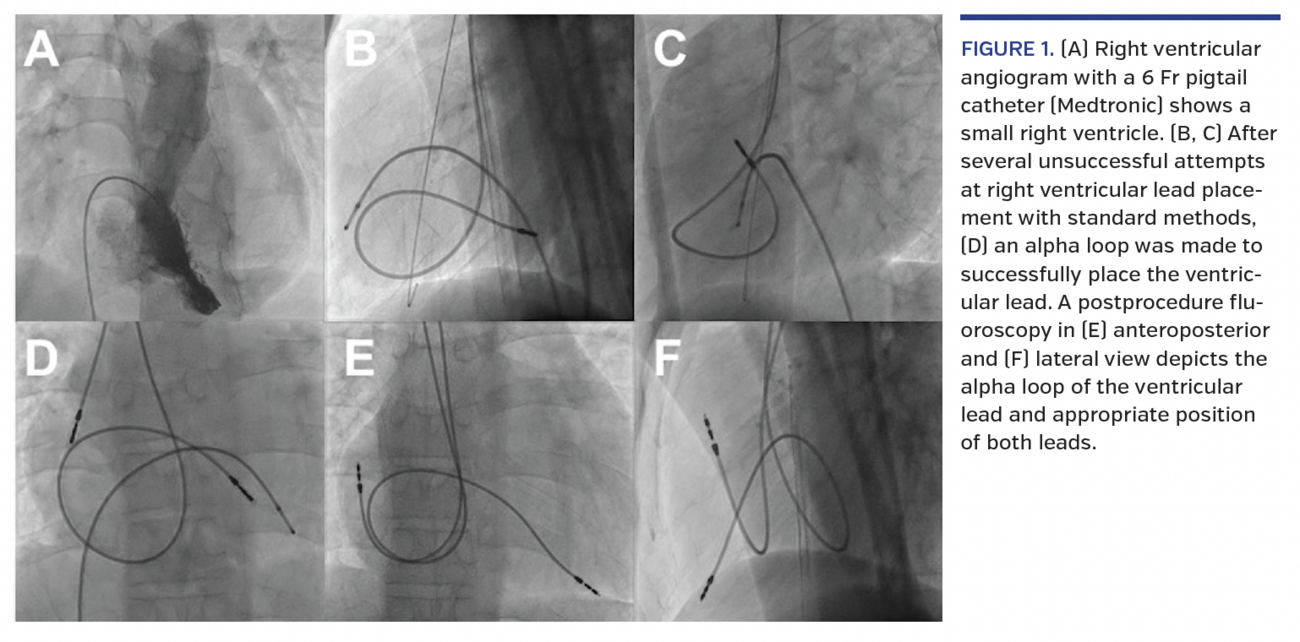

A 22-year-old male patient, diagnosed with non-familial idiopathic restrictive cardiomyopathy on the basis of symptoms, transthoracic echocardiogram, cardiac magnetic resonance imaging, cardiac catheterization, and genetic testing, presented with recurrent episodes of syncope. A 24-hour ambulatory monitoring revealed high-grade atrioventricular block. A dual-chamber permanent pacemaker implantation with DDDR pacing was planned. After uneventful right axillary venous punctures, several attempts to place an active fixation ventricular lead (Biotronik) were unsuccessful (Figures 1B and 1C) as the lead failed to prolapse across the tricuspid valve due to the hugely dilated right atrium and a small right ventricle (Figure 1A). An alpha loop was made in the right atrium to negotiate the tricuspid valve and enhance the lead stability (Figure 1D). After the confirmation of appropriate thresholds and impedance, the lead was screwed at the ventricular apex. The positioning of the right atrial lead was uneventful. A postprocedure on-table fluoroscopy (Figures 1E and 1F) and x-ray after 24 hours depicted the alpha loop and appropriate lead position. At 3-month follow-up, the patient was symptomatically better and device interrogation showed stable lead parameters. High-grade and complete heart block commonly occurs in adult patients with restrictive cardiomyopathy, and requires aggressive monitoring and prophylactic pacemaker/defibrillator. There are limited data on the procedural details of pacemaker implantation in this group of patients, and as reported, special maneuvers may be required for ventricular lead placement.